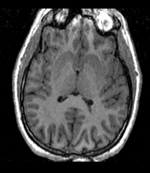

Input

this is the fixed reference image. All images are aligned into this space

RegArrow NonRigid.png

this is the moving target image, to be aligned with the reference image on the left

fixed image/target

T1

moving image

group atlas